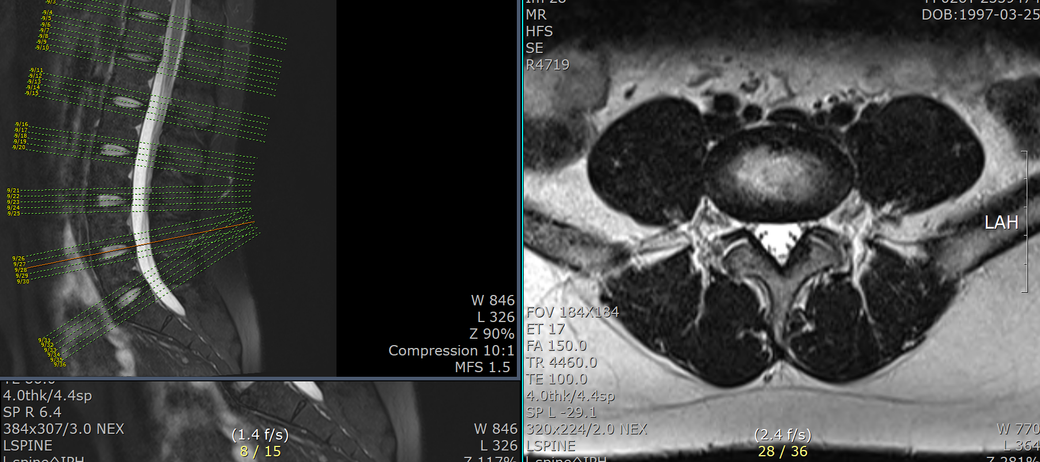

mri 판독 결과 남깁니다..

T12-L1 level에서 disc가 뒤쪽 Lt. central aspect로 protrusion되어 있고 mild한 dural sac indentation을 주고 있음.

그 외 disc level과 neural foramen에서 definite한 abnormality는 보이지 않음.

• 2번 째 사진

아래 사진에 있는 부위가 아마 T12/L1 사이에 디스크가 살짝 뒤로 빠져있다는 부위이실겁니다.

옆에서 보면 두번째 사진이구요.

우선은 이 디스크 내장증으로 인한 연관통으로 보고 요추전만 자세를 잘 실천해보시는게 가장 우선 필요한 조치이겠습니다.

수술을 주로 다루는 신경외과, 정형외과 선생님들의 경우에 심한 디스크탈출 및 신경뿌리를 누르는 신경뿌리병증이 생길만한 병변만 통증을 유발한다고 보시기 때문에 문제될만한 병변이 없다고 이야기 하셨을텐데 저렇게 작게 찢어진 디스크 때문에도 충분히 통증이 생길 수 있습니다. 물론 찢어진 디스크의 위치에 비해 통증이 밑에 있는 편이시지만 이게 불가능한건 아닙니다. 디스크 내장증이라고 하며 이럴때는 요추전만 자세가 가장 중요합니다.